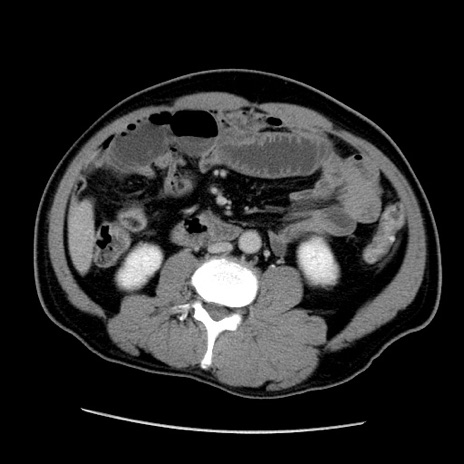

症例22(横断像)

【症例】50歳代男性

【主訴】腹痛

【現病歴】AVMからの被殻出血のため回復期リハ病棟入院中。 本日午後3時頃急に下腹部痛が出現した。

【既往歴】AVM、被殻出血、虫垂炎、高血圧

【身体所見】意識晴明、左半身不全麻痺、会話の理解は良好、36.5°C、腹部:膨隆、全体に板状硬、下腹部正中に圧痛点あり、反跳痛-、筋性防御不明、右下腹部にope scar

【データ】WBC 9400、CRP 0.06